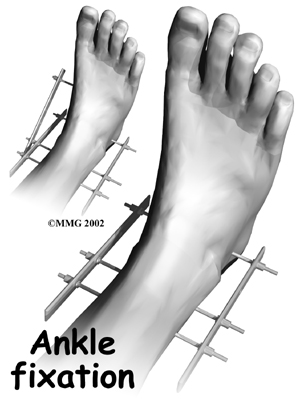

In some cases, especially if the fusion is being done because of an infection or a failed initial fusion, an apparatus called an external fixator is used to hold the bones together while they heal. This apparatus has metal pins that are inserted through the skin and into the bone. The metal pins are connected to metal rods and bolts outside the skin that hold the bones in position while the ankle fuses. The fixator is removed after the bones have healed, usually in 12 to 15 weeks.

External Fixator

Ankle Fuses